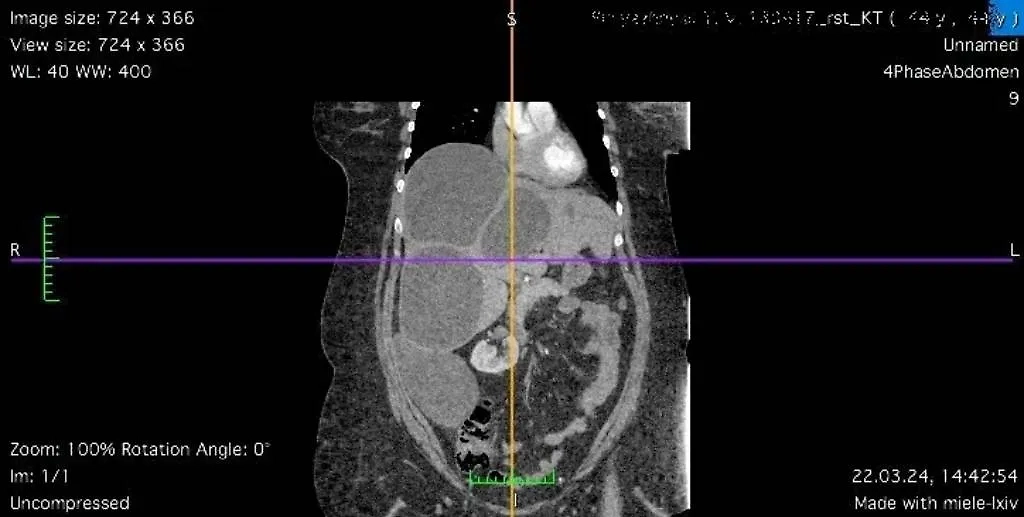

Снимок, полученный при проведении спиральной компьютерной томографии у пациентки из Луганска, которую спасли ростовские врачи. Фото © РостГМУ

"Обнаружен значительный объём поражения печени эхинококкозом — практически всей правой и части левой доли. Четыре крупных эхинококковых кисты заместили более 50% ткани печени", — отметил доктор медицинских наук, профессор, завкафедрой оперативной хирургии и топографической анатомии РостГМУ Юрий Хоронько.